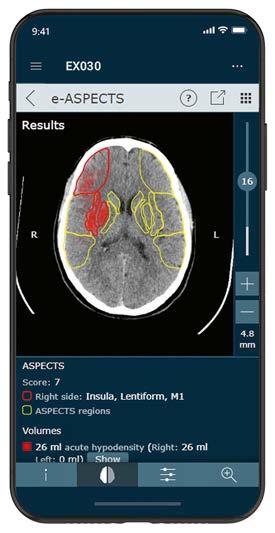

Die 3DQuorum-Bildgebungstechnologie mit Genius AI ist in der DACH-Region verfügbar 54 Die diagnostischen Referenzwerte im Fokus Flächendosismessystem erfasst die individuellen Patientendosismesswerte, um Einhaltung der DRWs zu überwachen X -EMPEL 26 Wahre Größe Der Computertomograph Aquilion Exceed LB von Canon Medical setzt neue Standards 58 KI-basierte Schlaganfalldiagnostik

Sana Klinik Lübeck setzt auf die automatisierte Auswertung von CT-Scans mithilfe von Künstlicher Intelligenz 64 Optimale Geräteauslastung in Echtzeit

Webbasiertes Termin-Buchungssystem als Erweiterung des RIS 66 Schicke App

Information per Pushnachricht – so sieht Radiologie heute aus 68 Digitaler Wunschtermin